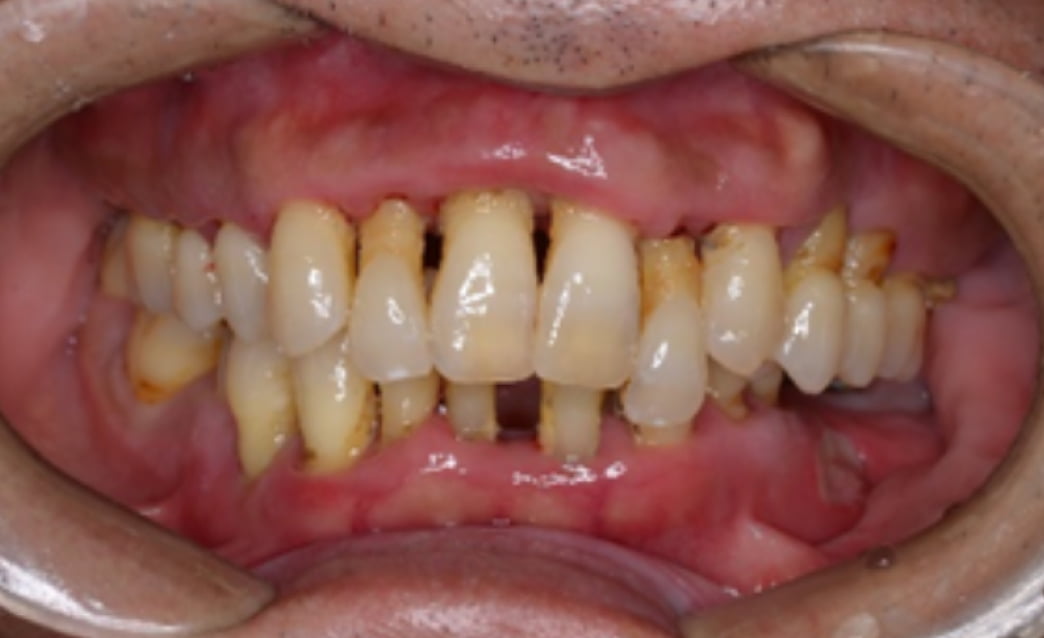

60代

Before

After

| 主訴 | 入れ歯が合わない。 |

| 治療内容 | 下顎の残存歯は、歯周病が進行していたため全て抜歯をおこない、同日にインプラント埋入と仮歯の装着をしました。骨とインプラントが固定されるのを約3ヵ月待ち、型どりをして最終補綴を装着します。上顎にはノンクラスプデンチャーを使用し、快適に食事がとれています。 |

| 治療期間 | 6ヵ月 |

| 費用 | ¥3,586,000(税込み) |

| リスク・副作用 |

外科処置が必要。コストがかかる。 |